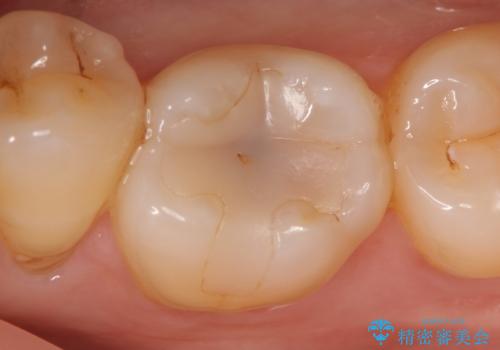

セラミックインレー 虫歯で欠けた歯の治療